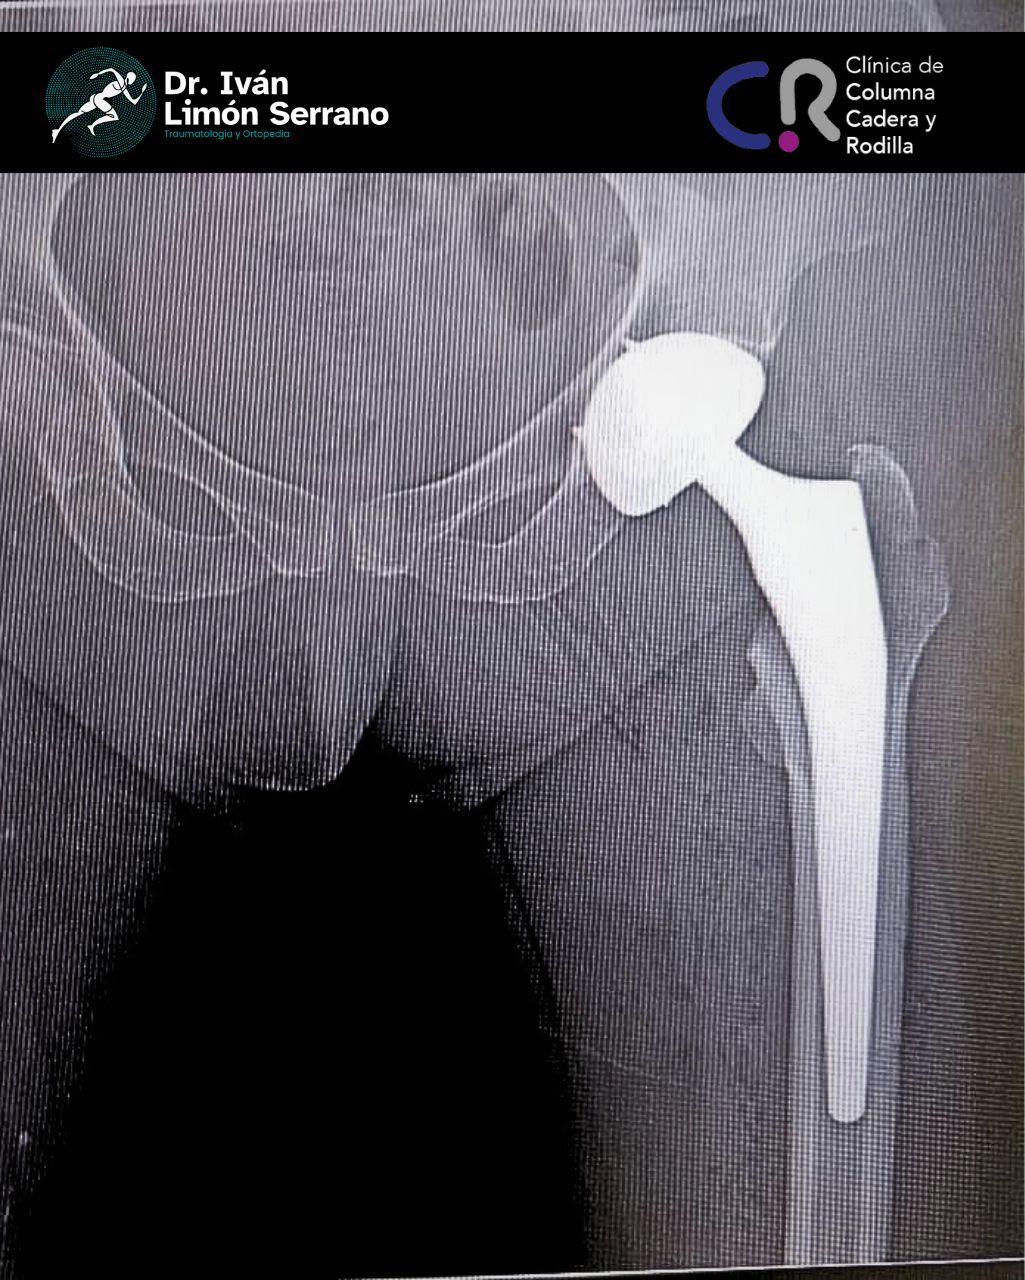

• Prótesis de cadera

• Cirugía cadera